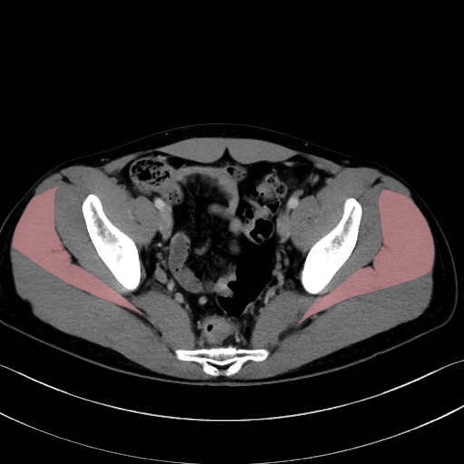

中殿筋 (Gluteus medius)